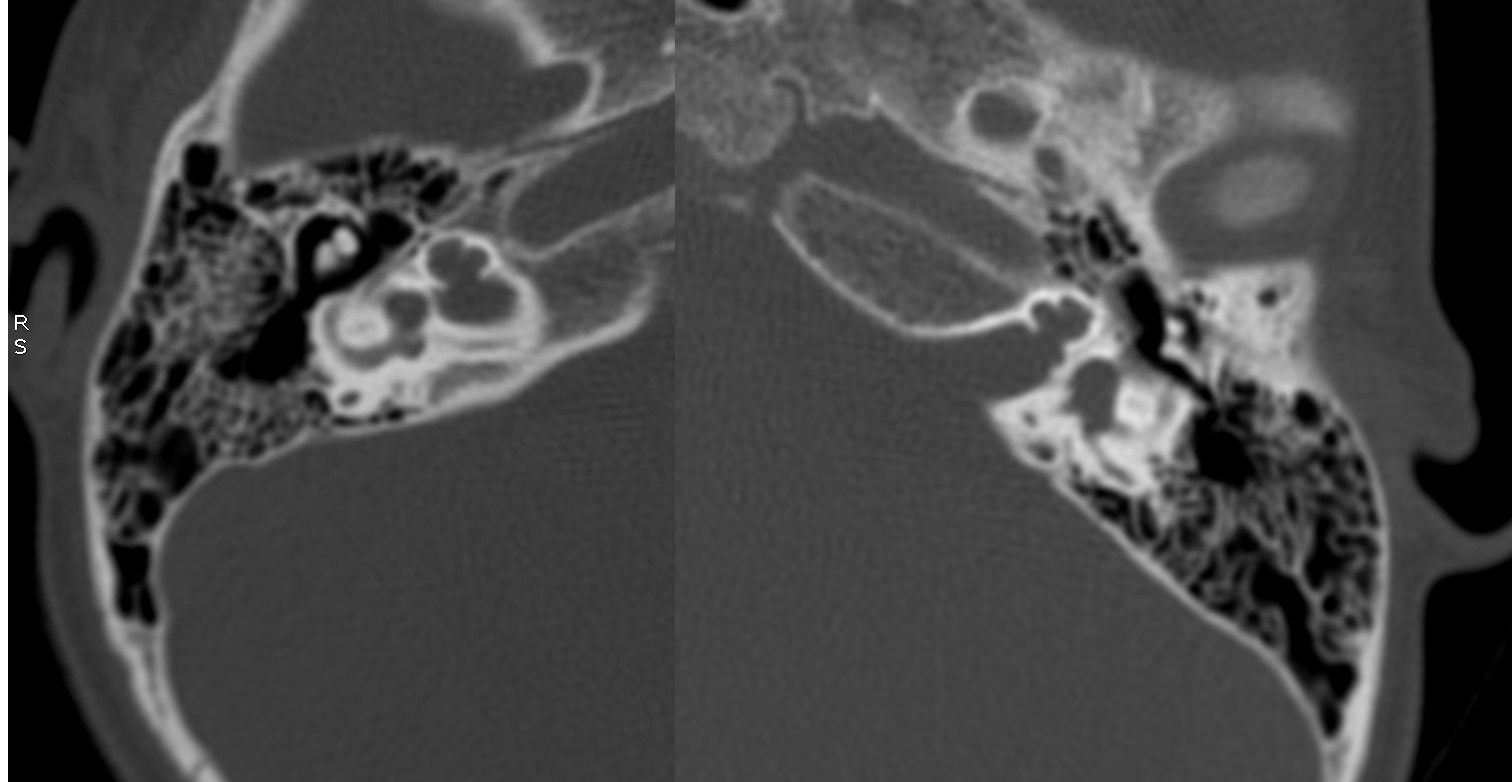

Evaluación de Imagen (TC)

Los hallazgos radiológicos, mediante TC de oídos a cuatro pacientes varones y una madre oyente, portadora obligada, se analizaron y clasificaron según Sennanoğlu et al. [8,9]. En ese sentido, son consistentes con PI-III en tres de ellos: IV-1, IV -2 y IV- 4. El paciente IV-3 mostró PI-I; la madre portadora obligada no mostró alteración alguna (Ver Tabla 3). En los cuatro pacientes estudiados de esta familia observamos dos tipos de MOI, PI-I y PI-III, incluso entre los hermanos IV-2 y IV-3, que presentaron diferente tipo de PI, lo que evidencia expresividad variable. La malformación PI-III es de las MOI menos frecuente y se encuentra presente en este estudio familiar como predominante.

| IV-1 | Ausencia de modiolo con presencia bilateral de septo interescalar | Discretamente amplio | Dilatación parcial en su segmento lateral | PI-III | Imagen 7 |

| IV-2 | De tipo quístico con ausencia bilateral de modiolo | Dilatado con hipoplasia de CSL izquierdo | Aparente estenosis de la entrada del nervio coclear al miodolo | PI-III | Imagen 8 |

| IV-3 | Ausencia de modiolo con presencia bilateral de septo interescalar | Dilatación en su segmento lateral | PI-I | Imagen 9 | |

| IV-4 | Ausencia de modiolo con presencia de septo interescalar bilateral | Discretamente amplio | Dilatación en su segmento lateral | PI-III | Imagen 10 |

| III-2 | Normal | Normal | Normal |

Abreviaturas: MOI: Malformación de oído interno; PI-III: partición incompleta de cóclea Tipo III; CSL: canal semicircular lateral; PI-I: partición incompleta de cóclea Tipo I.

| IV-3 | HNS media bilateral congénita | PI-I | 1, 2 y 9 |